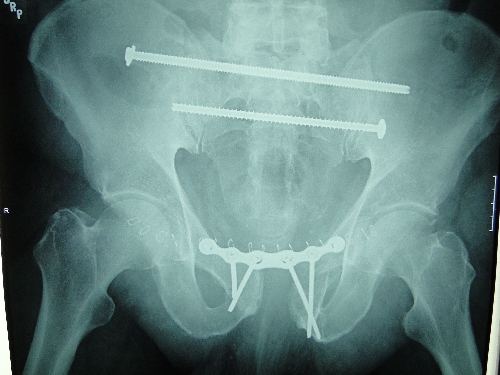

Gibbons' pelvis was broken in several places when he was thrown from a horse after he put one foot in a stirrup and began to put his other foot in the other stirrup.

Ten-inch and 8-inch bolts have been placed in his body temporarily, with several plates, to hold the pelvis together while it heals.